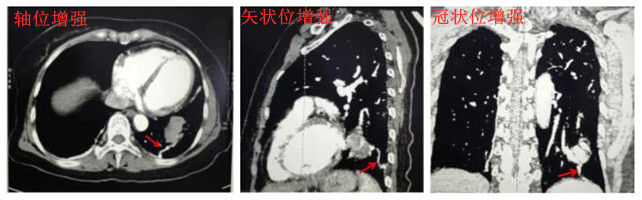

63岁女性患者,因右踝关节骨折住入我院骨伤科,无反复呼吸道感染及咯血病史,无咳嗽、胸痛、消瘦、乏力。入院后常规拍胸片意外发现左下肺心影后团块状高密度影,进一步行胸部CT示左肺下叶基底段团块状软组织密度影,形态不规则,有浅分叶,不除外肿瘤,建议CT引导下肺穿刺活检。内四科姚纲副主任医师会诊后建议行胸部CT增强扫描,用我院64排128层西门子螺旋CT增强扫描示病灶中度强化,三维重建示左下肺病灶由后肋间动脉供血,诊断为肺隔离症(叶内型)。

注:供血血管见红色箭头所指

肺隔离症(pulmonary sequestration)是一种少见的先天性肺发育异常,发病率为0.15%~6.4%。特点是病变组织不通过正常支气管与中央支气管相通,且接收异常体循环供血。根据隔离肺组织有无独立脏层胸膜,肺隔离症分为叶内型、叶外型和混合型,叶内型约占80%,多位于下叶后基底段,尤其是左下叶,常伴反复感染或咯血。叶内型肺隔离症多由降主动脉(约75%)供血,偶见冠状动脉、胸廓内动脉、肋间动脉、膈动脉等。肺隔离症为临床少见病,由肋间动脉供血的肺隔离症更为少见,极易误诊为肺癌、肺脓肿、肺囊肿等。该患者能及时确诊,得益于我院先进的影像设备及医务人员精湛的业务技术。乱花虽欲迷人眼,难奈惠眼辨真凶,及时明确诊断,既解除了患者及家属的紧张恐惧心理,也避免了患者承受因不必要的肺穿刺活检带来的痛苦及风险。